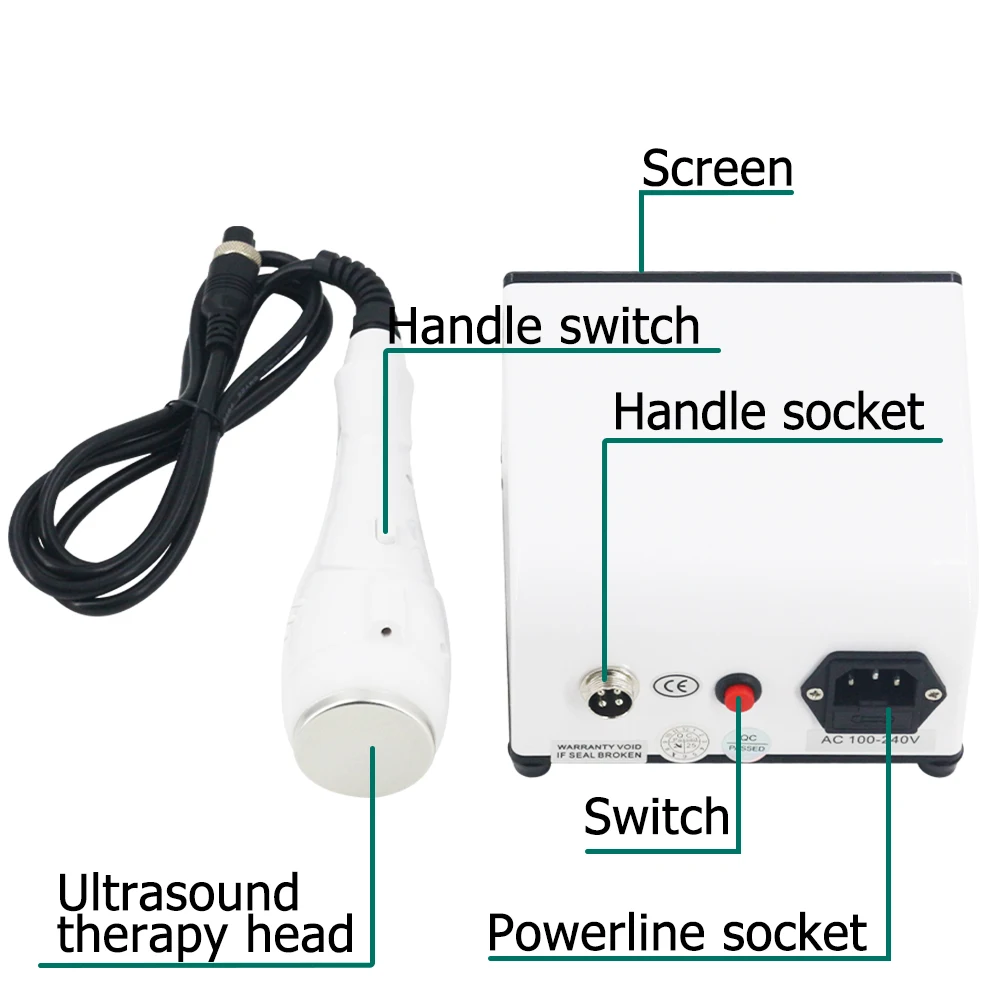

Convex Probe Pictures: